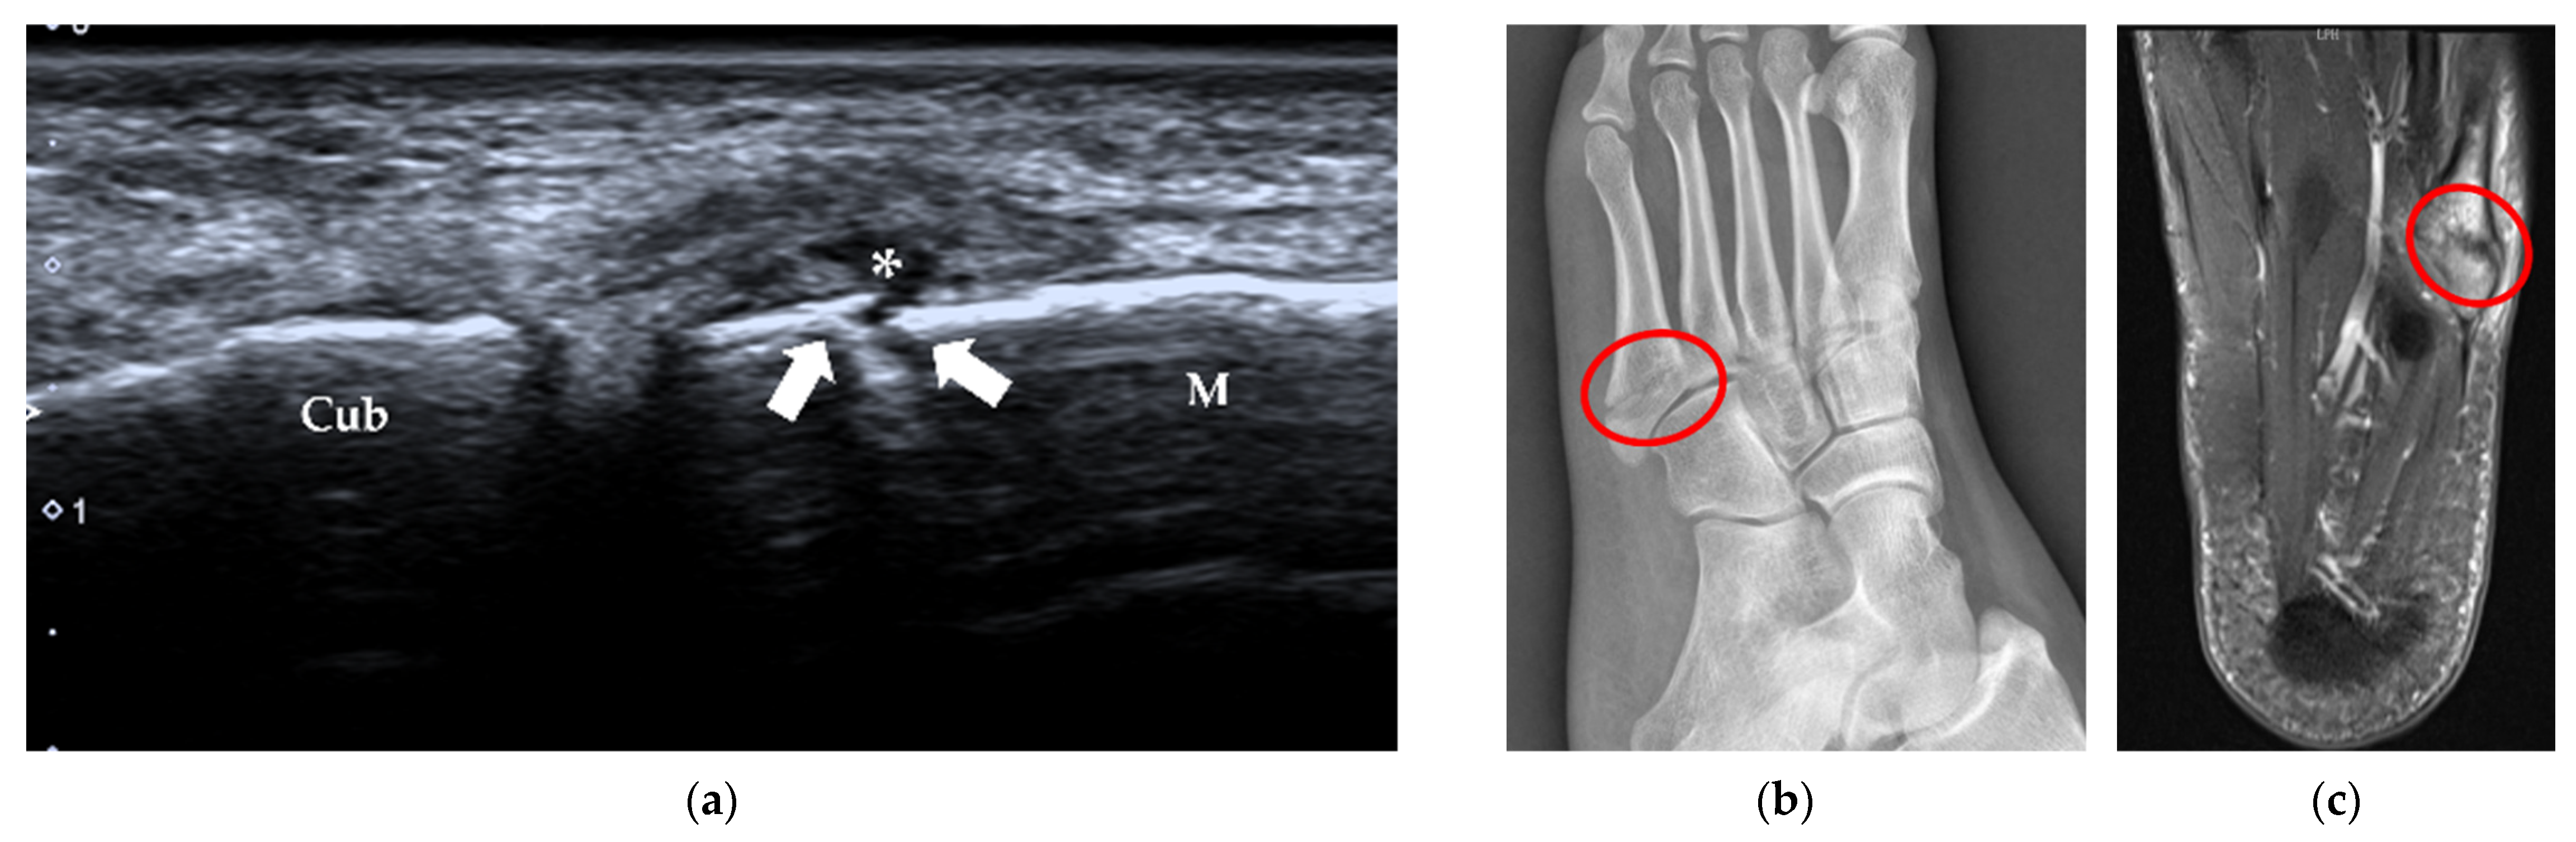

4.1.3. Stress Fracture

| Stress fracture | 2nd and 3rd metatarsals | periosteal lifting or cortical disruption, hypoechoic hematoma above the cortical bone |